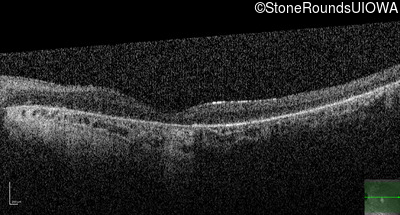

Optical Coherence Tomography - Left - 5/225

Exemplar / OCT Stack

OCT Stack